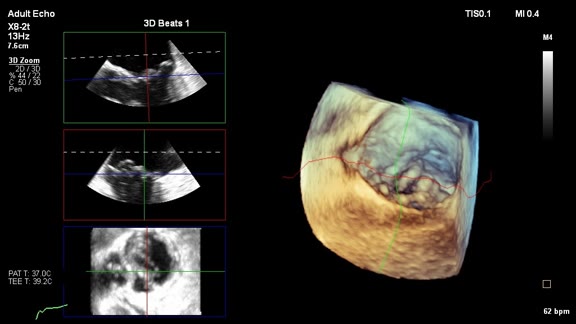

Frontiers Intraoperative Ultrasound Emerging Technology And Novel Applications In Brain Tumor Surgery